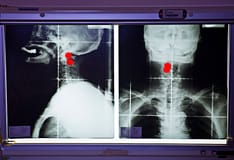

Imaging studies can be useful in assessing primary lesions and in evaluating cervical metastases.

Computed tomography (CT) scans, generally with intravenous contrast administration, are often useful in detecting the extent of tumor infiltration into deep musculature and the involvement of adjacent bone. CT scans are also useful as an indicator of malignancy in a cervical lymph node. Although various authors report a size of 1.2-1.5 cm as suggestive of malignancy, necrosis is a much more reliable indicator.

Ultrasonography is less sensitive in the detection of cervical lymph node metastases, and magnetic resonance imaging (MRI) is as sensitive as CT in a comparison of the 3 modalities. The least accurate method for detecting cervical metastases is palpation.